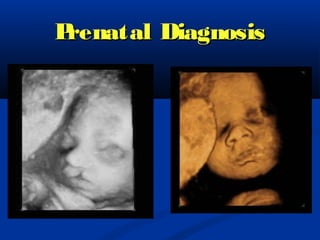

Prenatal Diagnosis  Diagnosed until the soft tissues of the fetal face can be clearly visualized sonographically (13 to 14 weeks).  The majority of infants with cleft lip also have palatal involvement:

• 12.